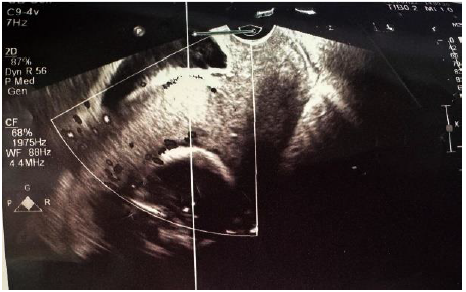

In the operating room, a midline incision was extended above the umbilicus due to severe adhesions. Given the extensive placental invasion, a fundal incision was performed to deliver the fetus. A breech female infant weighing 1690 grams with an Apgar score of 8-9 was delivered during a two-hour-long cesarean delivery operation. Due to severe lower uterine segment adhesions, a hysterectomy was performed (Figure 3). The placenta was not removed and was kept in situ. The uterus and placenta were successfully removed intact, with the cervix visible, as shown in the attached images (Figure 4). The cervix was clearly identifiable, and both ovaries were preserved, considering the patient’s age. Estimated intraoperative blood loss was approximately 2,000 ml, and one unit of packed red blood cells was transfused based on an anesthesiologist’s assessment. The fully extracted placenta was transferred to the pathology laboratory for further study. The patient had an uneventful postoperative recovery and was discharged from the hospital on postoperative day 3.

Figure 3. Intraoperative photograph showing placental infiltration into the uterine wall and bulging of the anterior surface, consistent with placenta percreta